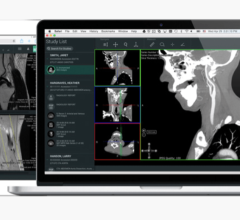

Even before the pandemic began to spread, the idea of offering radiologists the flexibility to work from home was trending. When COVID-19 enforced social distancing and new work behavior, it kicked this trend into high gear. Working from home helps limit exposure to the virus while still allowing radiologists to read as if they were on-site. The first challenge is creating home reading solutions that are the same level of quality, security and performance radiologists get from a medical workstation in the hospital reading room. The second challenge is getting them set up in a timely manner.

Barco and VisionTek partnered to develop a solution specifically designed for remote radiology reading that tackles both challenges. Together, they are undertaking the issues of technology compatibility and performance, security and patient privacy, as well as quality and compliance. Their home read solution has attracted immediate attention and early adoption in the hospital community.

The VisionTek Thunderbolt 3 Mini eGFX Enclosure comes in a sleek and portable design that discretely sits on a desk, or hidden away, to handle graphic intensive medical scan applications. Combined with a pre-installed Barco MXRT-display controller, VisionTek’s Thunderbolt 3 Mini eGFX Enclosure can accelerate the most demanding medical scan software programs.

“This configuration is seamlessly deployable and mirrors the hospital reading environment providing the same diagnostic confidence and medical compliance maintained within hospital walls,” reported Mike Sklar, VP Healthcare Sales for the Americas at Barco. “It’s paired with Barco’s QAWeb Calibration and Monitoring Software, which is the industry's first and only web-based service for high-grade Quality Assurance.”

"VisionTek’s Mini eGFX enclosure powered by Barco MXRT series graphics boards and diagnostic displays allow Radiologists to remotely read scans in the safety of their home office." stated Michael Innes, President, VisionTek Products, LLC. “VisionTek is very proud to play a small part in technology innovation that impacts some of the most critical healthcare applications within the radiology community.”